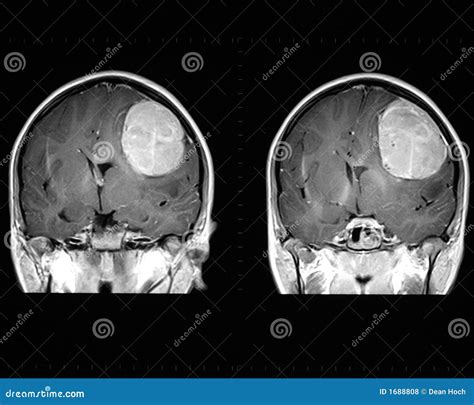

When a physician suspects an abnormality within the skull, a Brain Neoplasm MRI is the gold standard diagnostic tool used to visualize the intricate structures of the brain. Neoplasms, or abnormal tissue growths, can be benign or malignant, and magnetic resonance imaging (MRI) provides unparalleled detail to distinguish between these possibilities. By utilizing powerful magnets and radio waves rather than ionizing radiation, MRI technology produces high-resolution, cross-sectional images that allow radiologists and neurosurgeons to pinpoint the exact location, size, and characteristics of a potential tumor.

• Location: Exactly where is the lesion situated relative to vital structures?

• Extent: Is the tumor localized, or is it infiltrating surrounding tissues?

• Edema: Is there significant swelling surrounding the mass?

Interpreting the Results